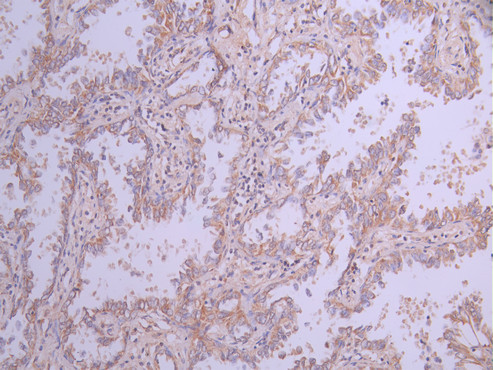

• IHC image of CSB-RA018656MA1HU diluted at 1:50 and staining in paraffin-embedded human lung cancer performed on a Leica BondTM system. After dewaxing and hydration, antigen retrieval was mediated by high pressure in a citrate buffer (pH 6.0). Section was blocked with 10% normal goat serum 30min at RT. Then primary antibody (1% BSA) was incubated at 4°C overnight. The primary is detected by a Anti-Human lgG, Fcy Fragment Specific labeled by HRP and visualized using 0.05% DAB.